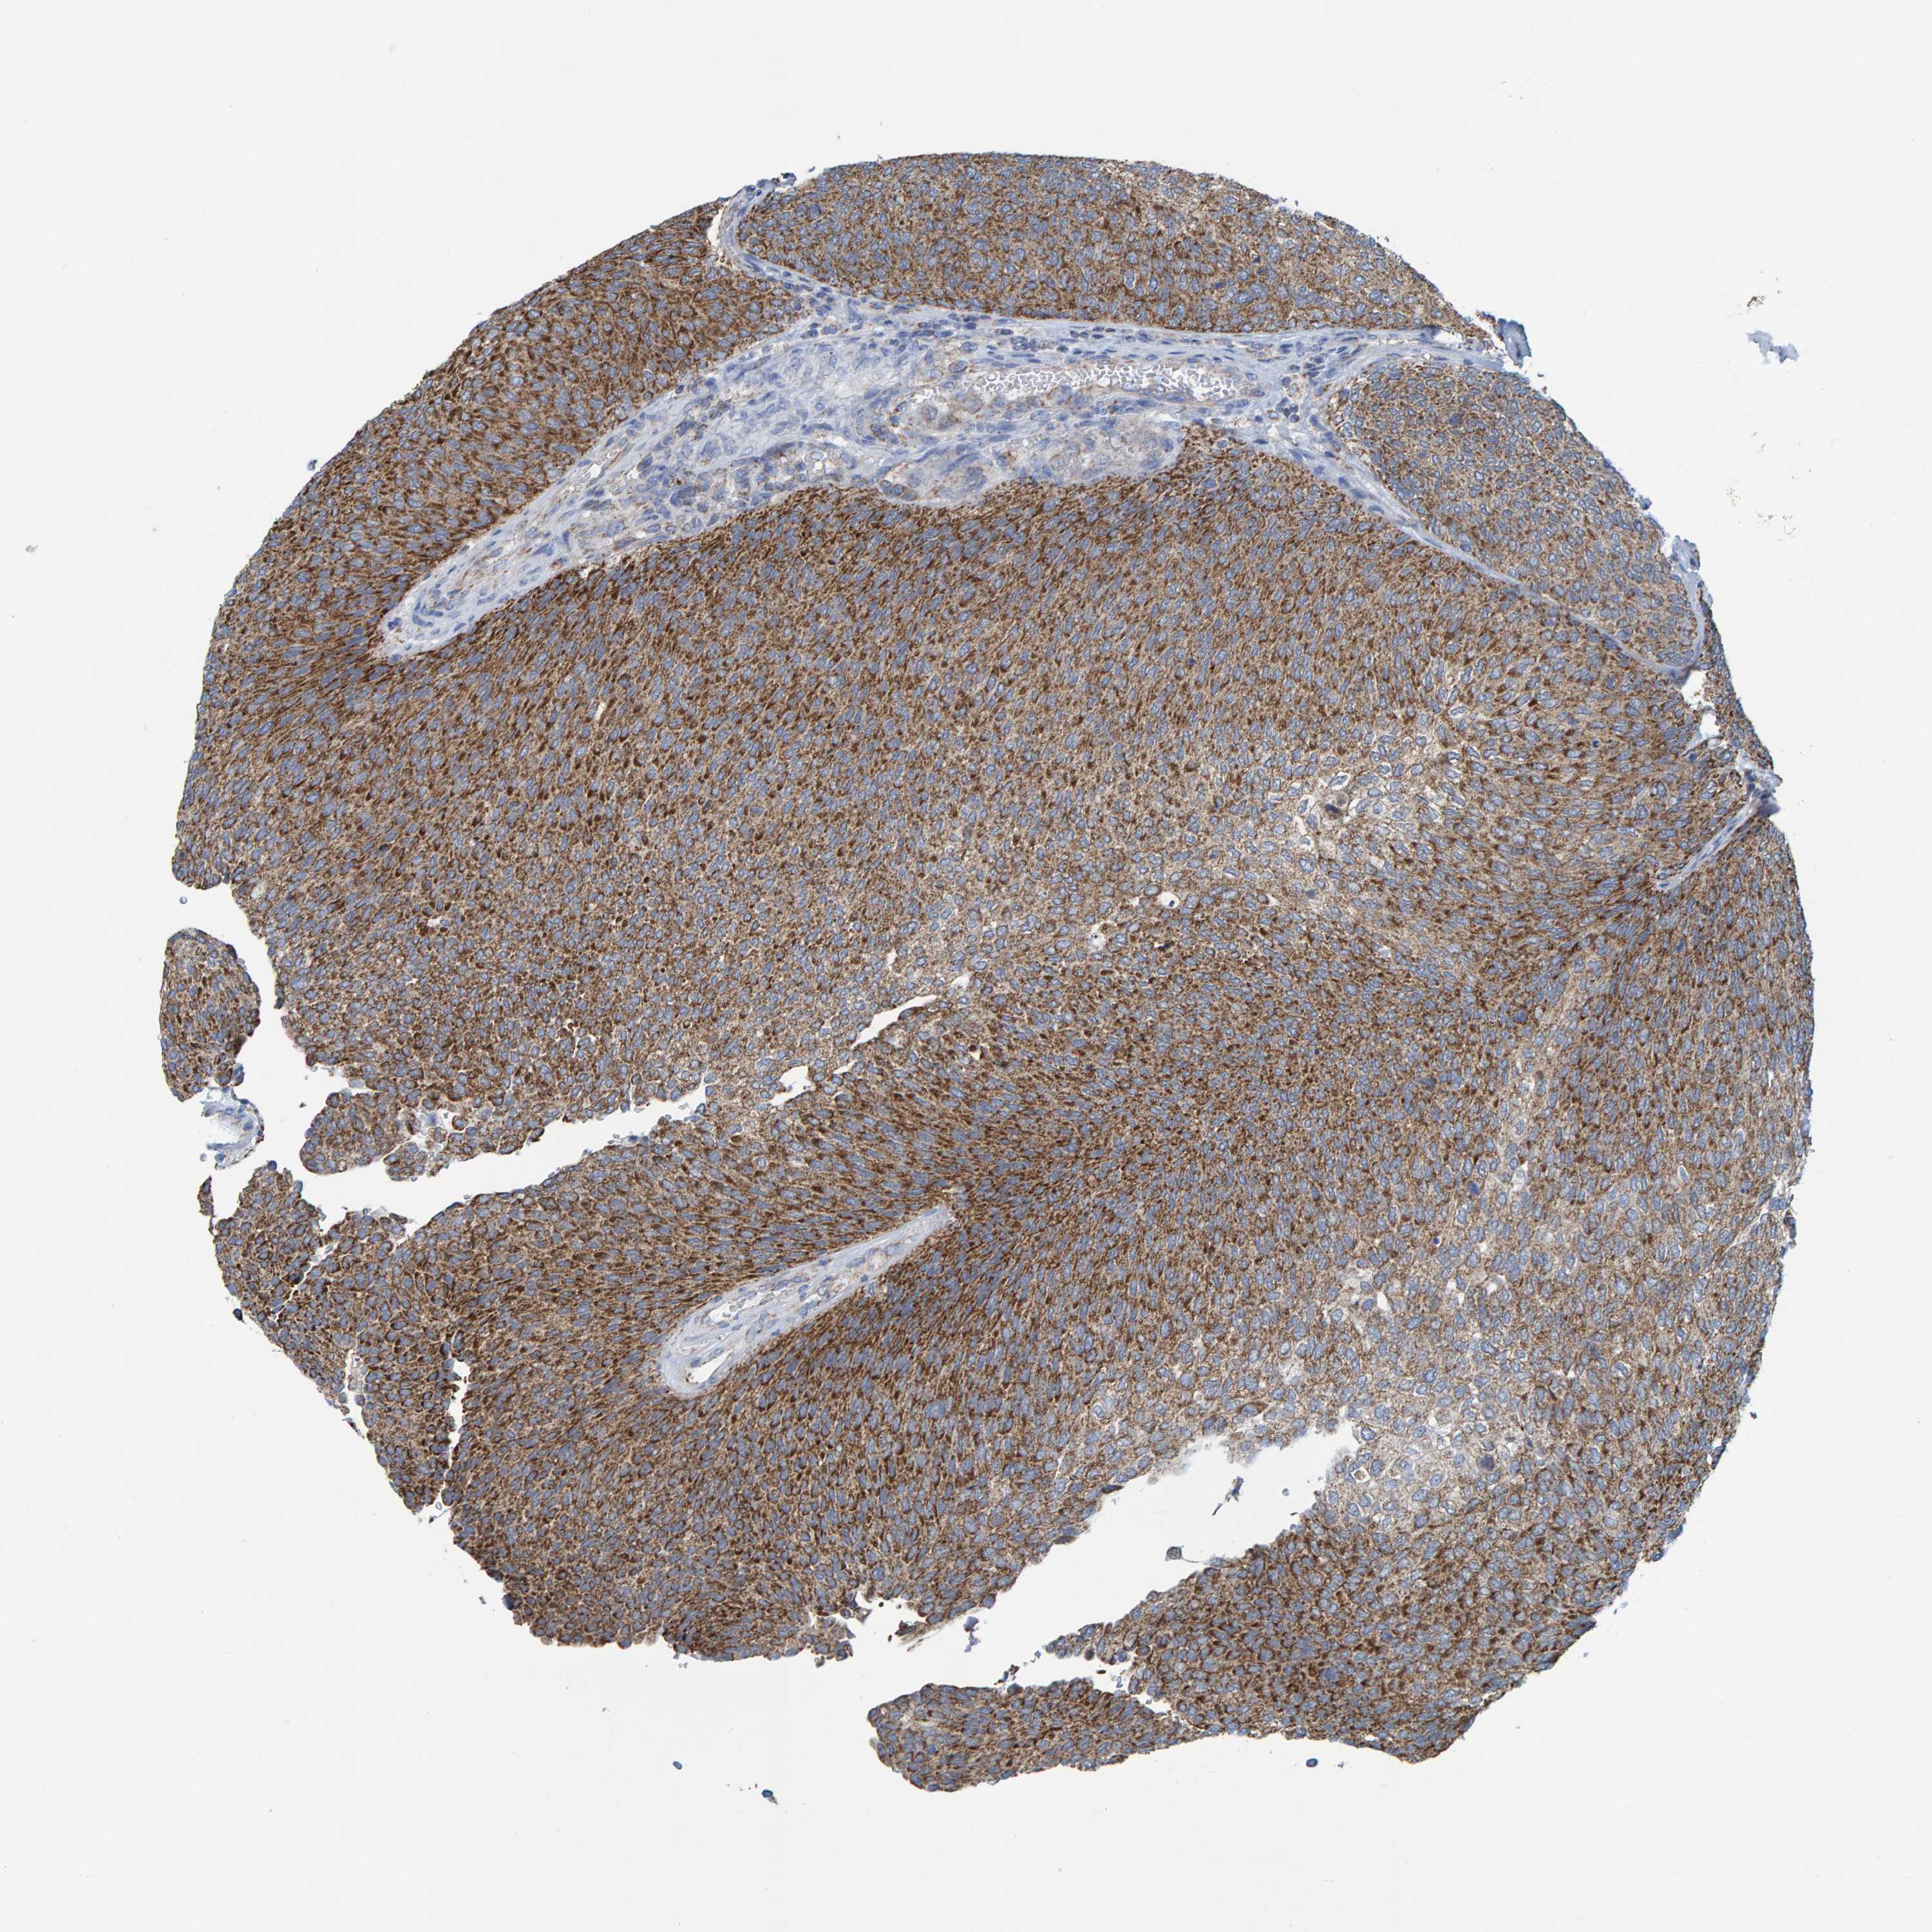

UROTHELIAL CANCER - Protein expressioni

A mouse-over function shows sample information and annotation data. Click on an image to view it in a full screen mode. Samples can be filtered based on level of antibody staining by selecting one or several of the following categories: high, medium, low and not detected. The assay and annotation is described here.

Note that samples used for immunohistochemistry by the Human Protein Atlas do not correspond to samples in the TCGA dataset.

Antibody stainingi

Antibody staining in the annotated cell types in the current human tissue is reported as not detected, low, medium, or high, based on conventional immunohistochemistry profiling in selected tissues. This score is based on the combination of the staining intensity and fraction of stained cells.

Each image is clickable and will lead to virtual microscopy that enables deeper exploration of all samples and also displays staining intensity scores, fraction scores and subcellular localization as well as patient and tissue information for each sample.

Antibody HPA022522

Antibody HPA023007

Staining

High

Medium

Low

Not detected

Intensity

Strong

Moderate

Weak

Negative

Quantity

>75%

75%-25%

<25%

None

Location

Nuclear

Cytoplasmic/membranous

Cytoplasmic/membranous,nuclear

Urothelial carcinoma, Low grade

Urothelial carcinoma, High grade